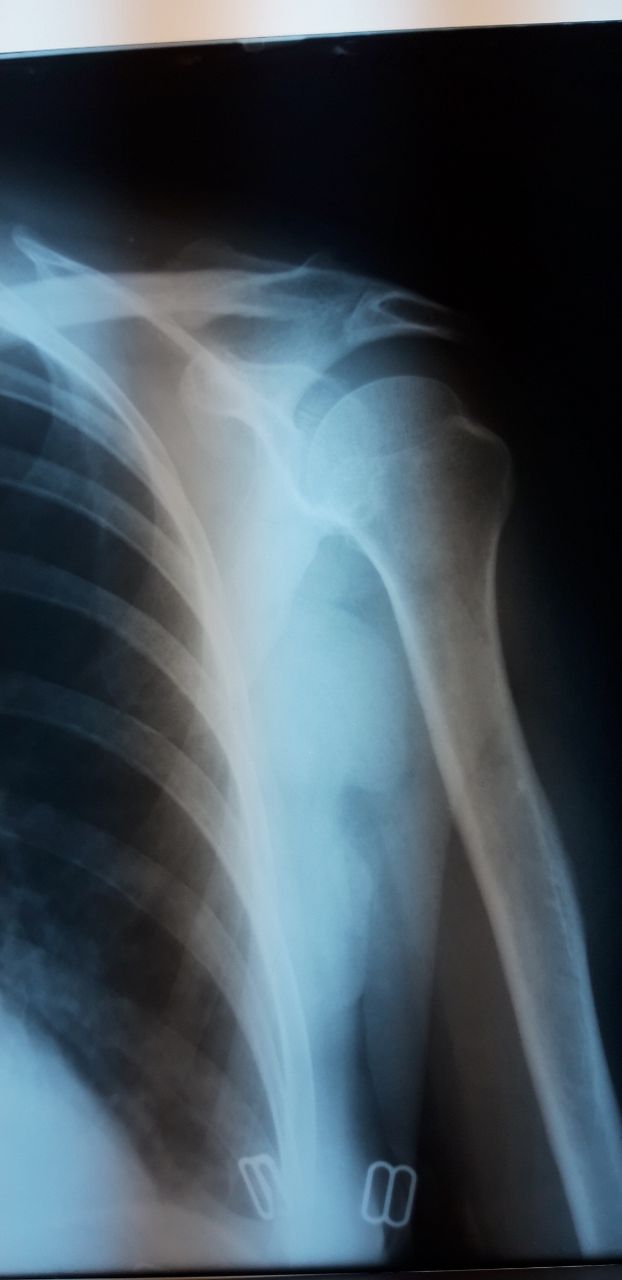

Коллеги,доброе утро.Не подскажите,есть ли перелом левой плечевой кости?для сравнения правое.Женщина 1945г

Смущает вот это место на плечевой кости

Хочется услышать ваше мнение

СПО?